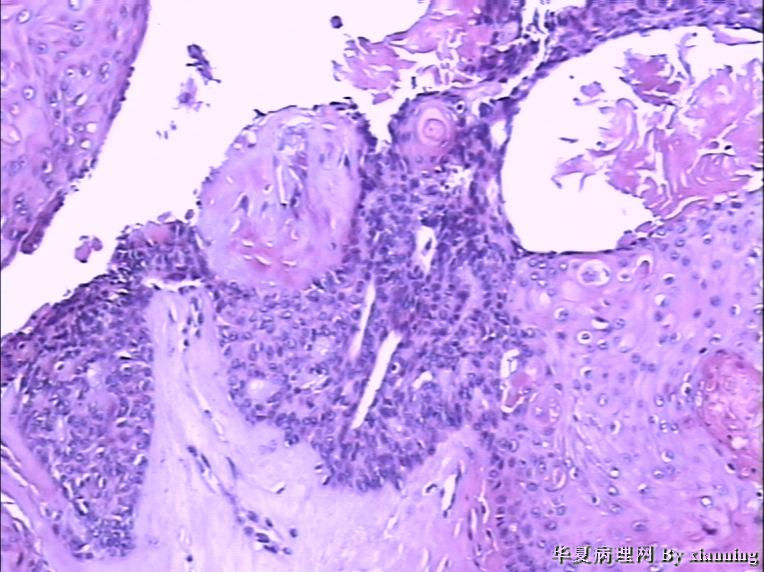

女 50岁 头皮下肿块

巨检:灰白色不规则结节0.9*0.7*0.4cm3,切面灰白色实性质地中等